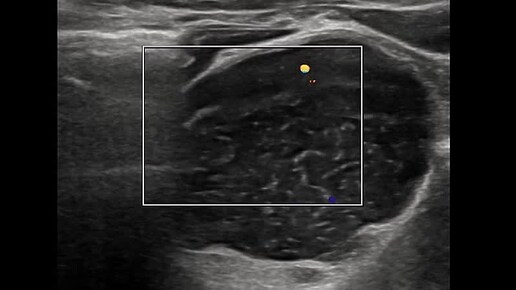

Видео к статье " ВНИМАТЕЛЬНОСТЬ И ЕЩЕ РАЗ ВНИМАТЕЛЬНОСТЬ" https://dzen.ru/a/aT_UUVK2zBjCoQvs

Ультразвуковые находки от врача УЗД Зорина Я.П.